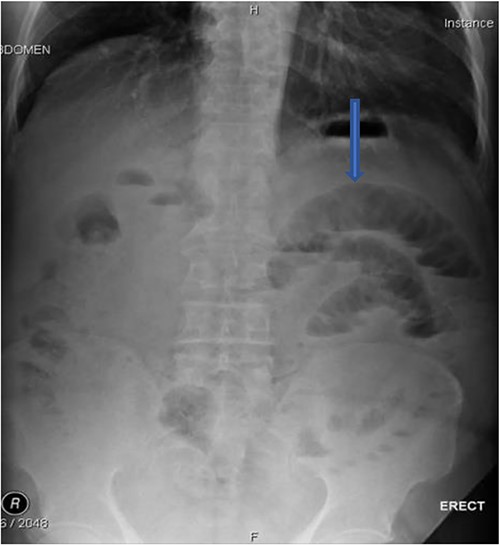

The plain film of the abdomen showed multiple air-fluid levels on the erect film (Fig. 1) and small bowel dilatation on the supine (Fig. 2). The CT showed multiple air pockets in the biliary tree, representing pneumobilia (Fig. 3). It also showed evidence of a circular radio-dense stone measuring 2 cm within the distal jejunum, leading to obstruction and dilatation of the proximal jejunum (Fig. 4).